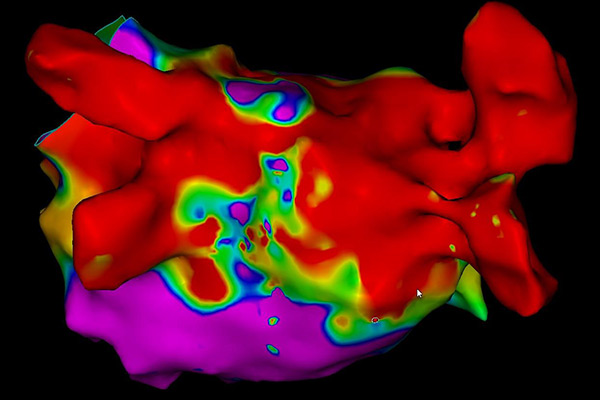

При електрофизиологичното изследване, посредством катетри (представляващи малки тръбички, които записват електрически сигнали) се прави точен запис на електрическите импулси в сърцето.

Изследването се извършва в т.нар. електрофизиологична лаборатория, в която се намира оборудването, необходимо за извършване на процедурата. В зависимост от аритмията се използва местна упойка, като при някои процедури се предпочита обща упойка (Вашият лекуващ лекар ще Ви уведоми за вида упойка, която ще бъде използвана). През вена на десния крак (понякога се налага използването на артерия) се въвеждат специални катетри (тръбички с диаметър под 3 мм), които записват директно електрическите сигнали от сърцето. По време на самото изследване сърцето се стимулира с електрически импулси, които Вие може да усетите като сърцебиене или по-силни сърдечни удари.

След като Вашият лекар е локализирал виновното за Вашата аритмия огнище се преминава към лечение – аблация. Посредством специален катетър се прилага енергия, наречена радиофреквентна енергия, която води до загряване и изгаряне на това огнище. Освен нагряване, при някои аритмии се използват специално пригодени балони или катетри, чрез които се постига замразяване на огнищата, водещи до аритмия, и тяхното елиминиране.